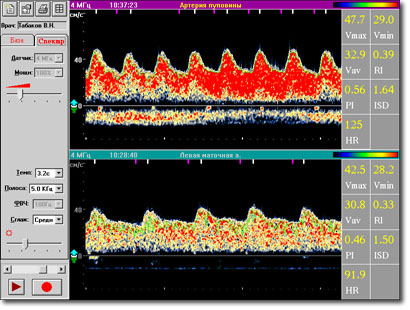

Суть метода состоит в изучении спектральных характеристик допплеровского сигнала при непосредственной локации сонных артерий. Получаемая в реальном масштабе времени спектрограмма состоит из точек разного цвета, совокупность которых дает спектр скоростей в поперечном сечении артерии за время сердечного цикла. Положение данной точки по отношению к оси ординат (шкала частот) соответствует определенной линейной скорости кровотока (выражаемой в соответствии с принципом Допплера в КГц), а ее цвет - удельному весу данной частоты в спектре (при максимальной интенсивности точка окрашивается в красный, при минимальной - в синий цвета).

Спектрограммы ВСА и НСА различаются по форме: спектрограмма НСА имеет острый систолический пик и низкую диастолическую составляющую, а спектрограмма ВСА - широкий систолический пик и значительно более высокую диастолическую составляющую (Рис 1.8).

Рис 1.8 Допплерограммы ВСА и НСА.